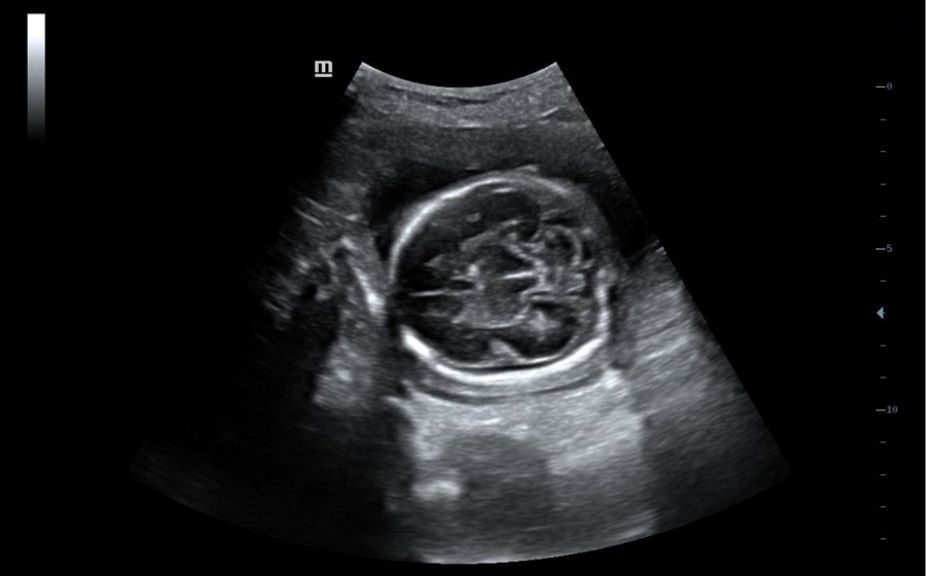

Klinik G?rĂŒntĂŒler